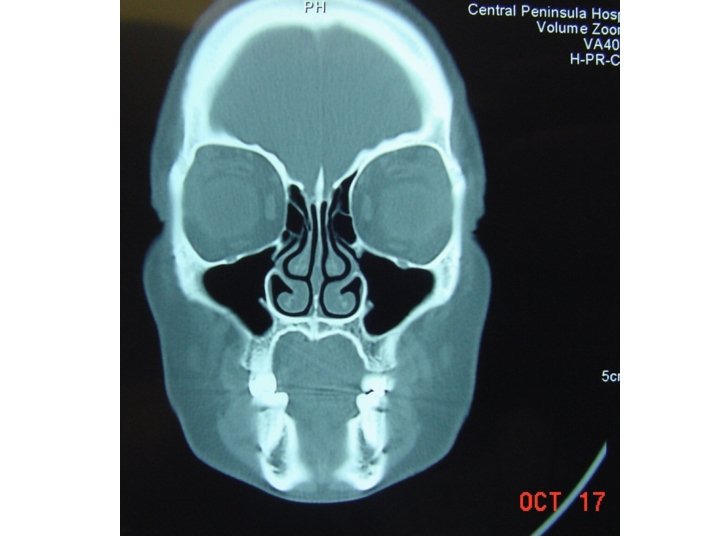

Ethmoid Sinusitis

Coronal computed tomographic scan showing ethmoidal polyps. Ethmoid opacity is total as a result of nasal polyps, with a secondary fluid level in the left maxillary antrum.